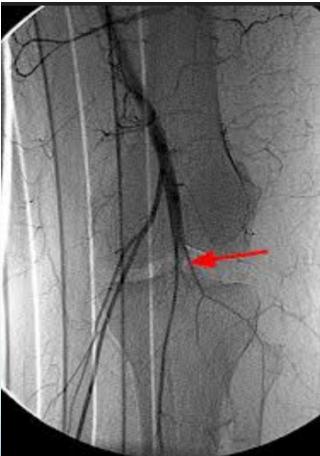

- Popliteal artery at risk

Vascular Assessment:

- Even if pulses are intact, perform angiography if there’s suspicion

- Angiography if distal pulses not felt

- Urgent reduction & vascular intervention if needed